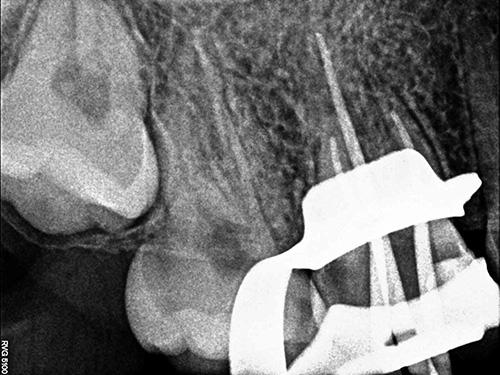

术前